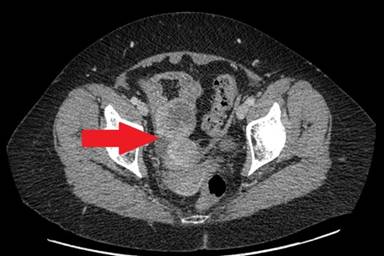

Five years after laparoscopic distal pancreatosplenectomy, surveillance glucagon levels showed a slight elevation whilst the patient remained otherwise well and asymptomatic. CT scanning showed a suspicious lesion in the distal small bowel, deep in the pelvis, with mucosal thickening and hyper-enhancement. This was thought to be a primary neuroendocrine tumour of the small bowel (Figure 4), as this would be regarded as an unusual site for recurrence of a primary pancreatic NET.

Figure 4. Cross sectional CT scanning demonstrating an abnormality in the pelvis, thought to be dilated terminal ileum with mucosal thickening and hyper-enhancement (red arrow). |

As there was uncertainty of the nature of the mass lesion in the distal small bowel, which was considered to be a most unusual site for glucagonoma recurrence, a laparoscopy was performed. At laparoscopy, the entire small bowel was examined and no lesion identified. However, the right ovary looked markedly abnormal and contained a large tumour, with no evidence of peritoneal disease, and no evidence of liver metastases. A laparoscopic right oophorectomy was performed and the patient made a good post-operative recovery and was discharged home.